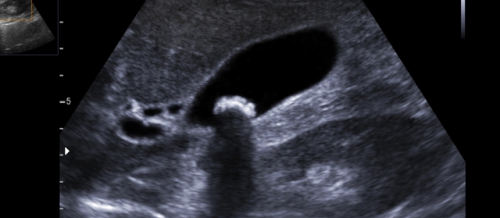

Ultrasəs nədir? Ultrasəs (sonoqrafiya və ya ultrasəs də deyilir) qeyri-invaziv görüntüləmə testidir. Ultrasəs şəklinə sonogram deyilir. Ultrasəs daxili orqanların və ya qan damarları kimi digər yum..

Ultrasəs müayinə (USM) və Doppleroqrafiya: Ultrasəs müayinə (USM) səs dalğalarından faydalanaraq daxili orqanların görüntüləmə üsuludur. Son illər ərzində, ultrasəs əvəzolunmaz bir müayinə olaraq t..

Ultrasonoqrafiya (USM) — ultradalğalı şüaların köməyi ilə həyata keçirilən tibbi müayinə növüdür. Rentgen şüaları kimi, ultradalğalı şüalar da toxumaların arasından keçir və sonra da ək..